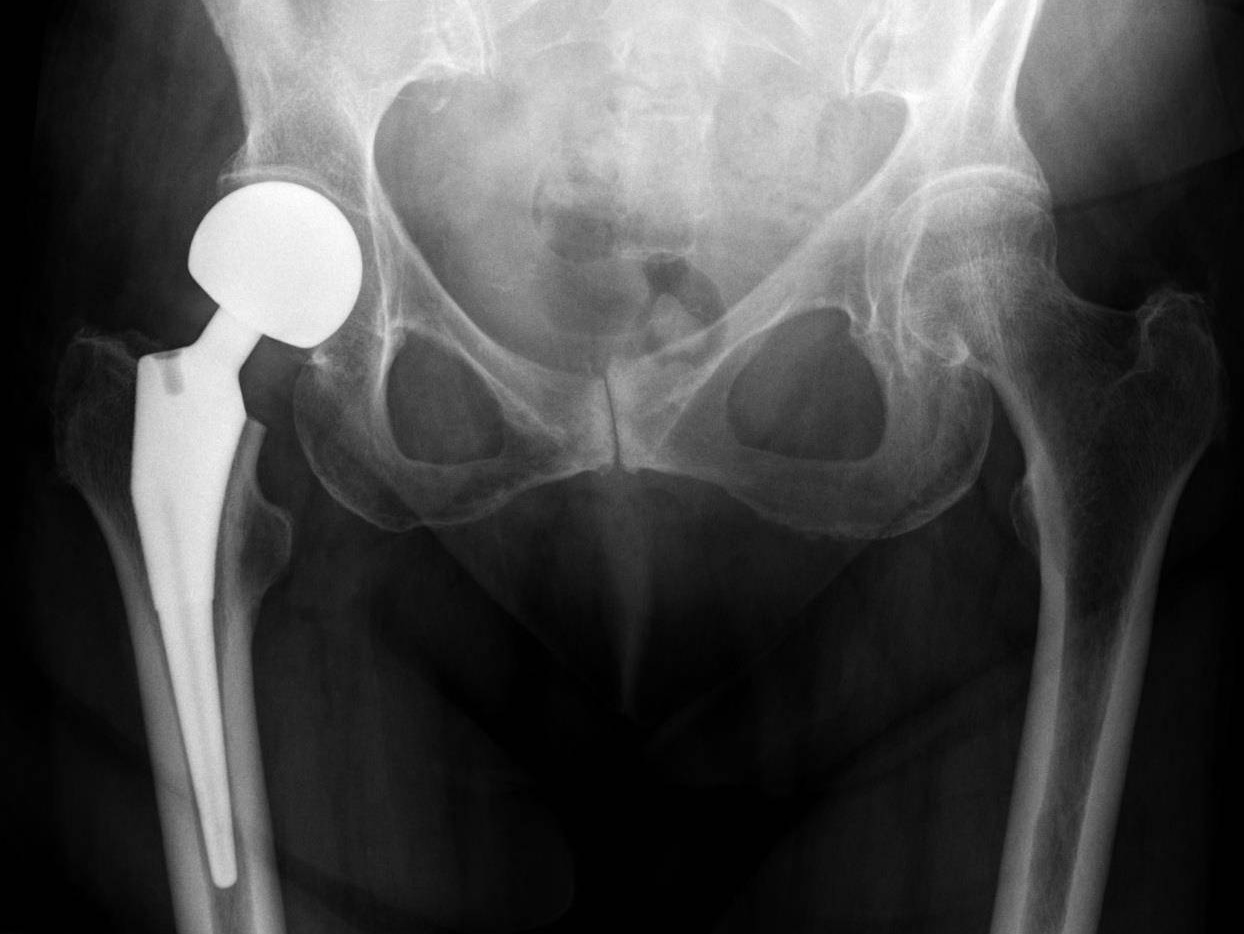

Cemented

A cemented hip replacement uses a polymethylmethacrylate (PMMA) bone cement to fix the implant surface to the bone. The bone cement creates a grout and fixes the implant by acting as an interlocking surface between the implant and the bone rather than simply gluing the implant to the bone.

Hemi Arthroplasty

A hip hemiarthroplasty is a surgical procedure where half of the hip is replaced. This procedure is typically used to repair a broken or fractured hip but can also be used to treat a hip damaged by arthritis.

Uncemented

Uncemented hips rely on biological fixation of bone to a surface coating on the prosthesis. Initial fixation is achieved by inserting a prosthesis slightly larger than the prepared bone-bed, generating compression hoop stresses, and obtaining a so-called “press-fit.”